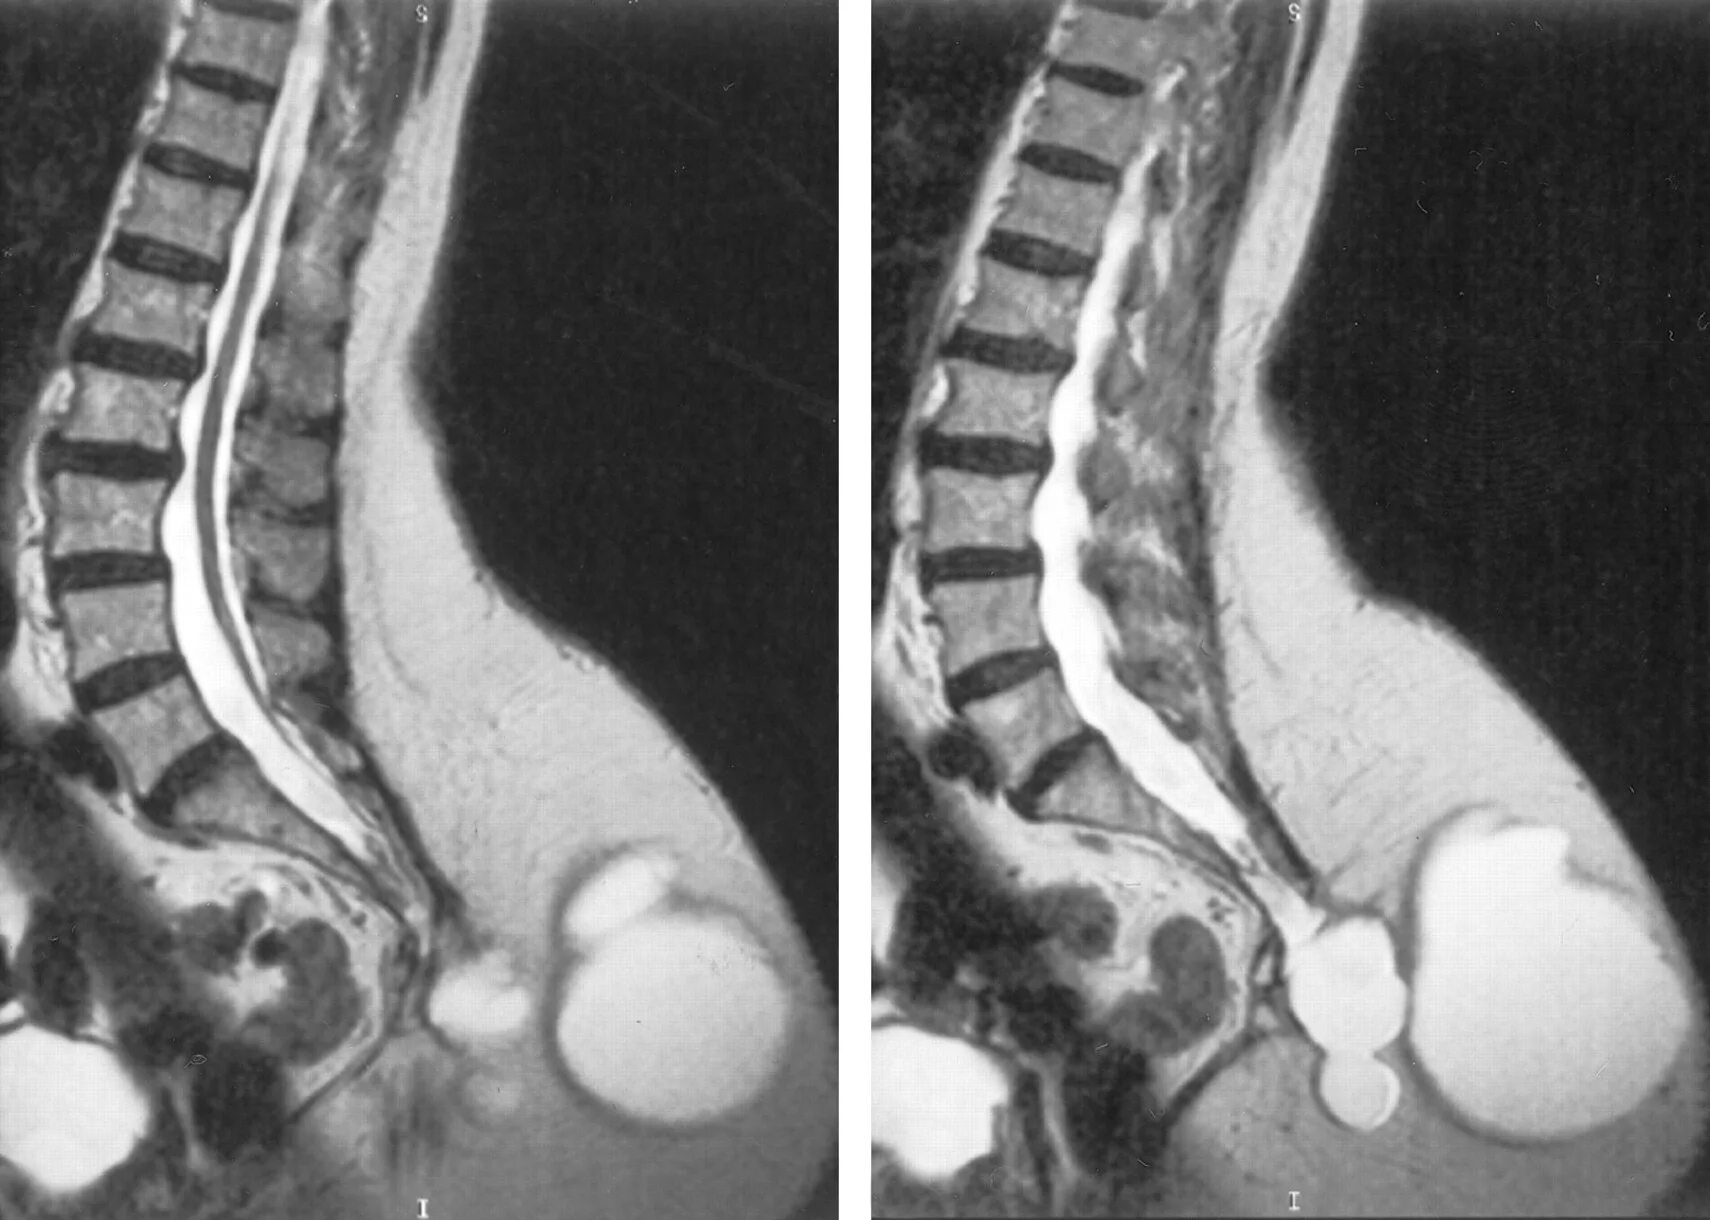

Спинномозговая грыжа